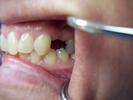

Implant replacement

This patient had their upper left first premolar replaced with a dental implant